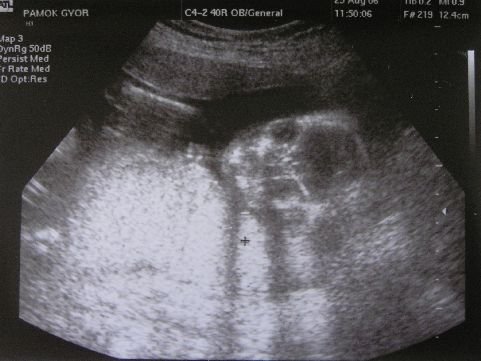

Jól értem, hogy kisfiút vársz? Készült kép? Ha igen, tedd fel kérlek!

Kép

Örülök, hogy mégsem nyíltál ki. Van képed amit feltehetsz?Ja és igen kisfiú, akkor bekékezlek:)

Havtünde! :) Csak nem pöcsös???? :lol: :lol: És nagyon édes :)